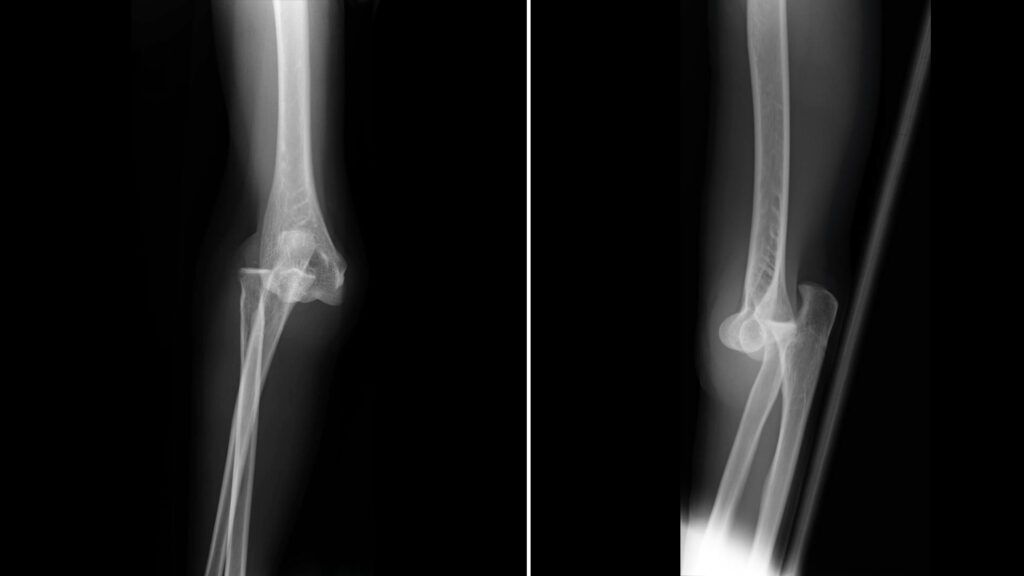

In the pursuit of high-performance endurance sports, athletes often concentrate on training protocols, pacing strategies, and performance metrics, neglecting to appreciate the psychological and physiological nuances that can heavily influence outcomes. Consider the example of Tara, a once-a-week bouldering enthusiast and a dedicated graphic designer. Her journey through a significant elbow dislocation and recovery process sheds light on critical aspects that can resonate with endurance athletes, especially those who frequently train under stressful conditions.